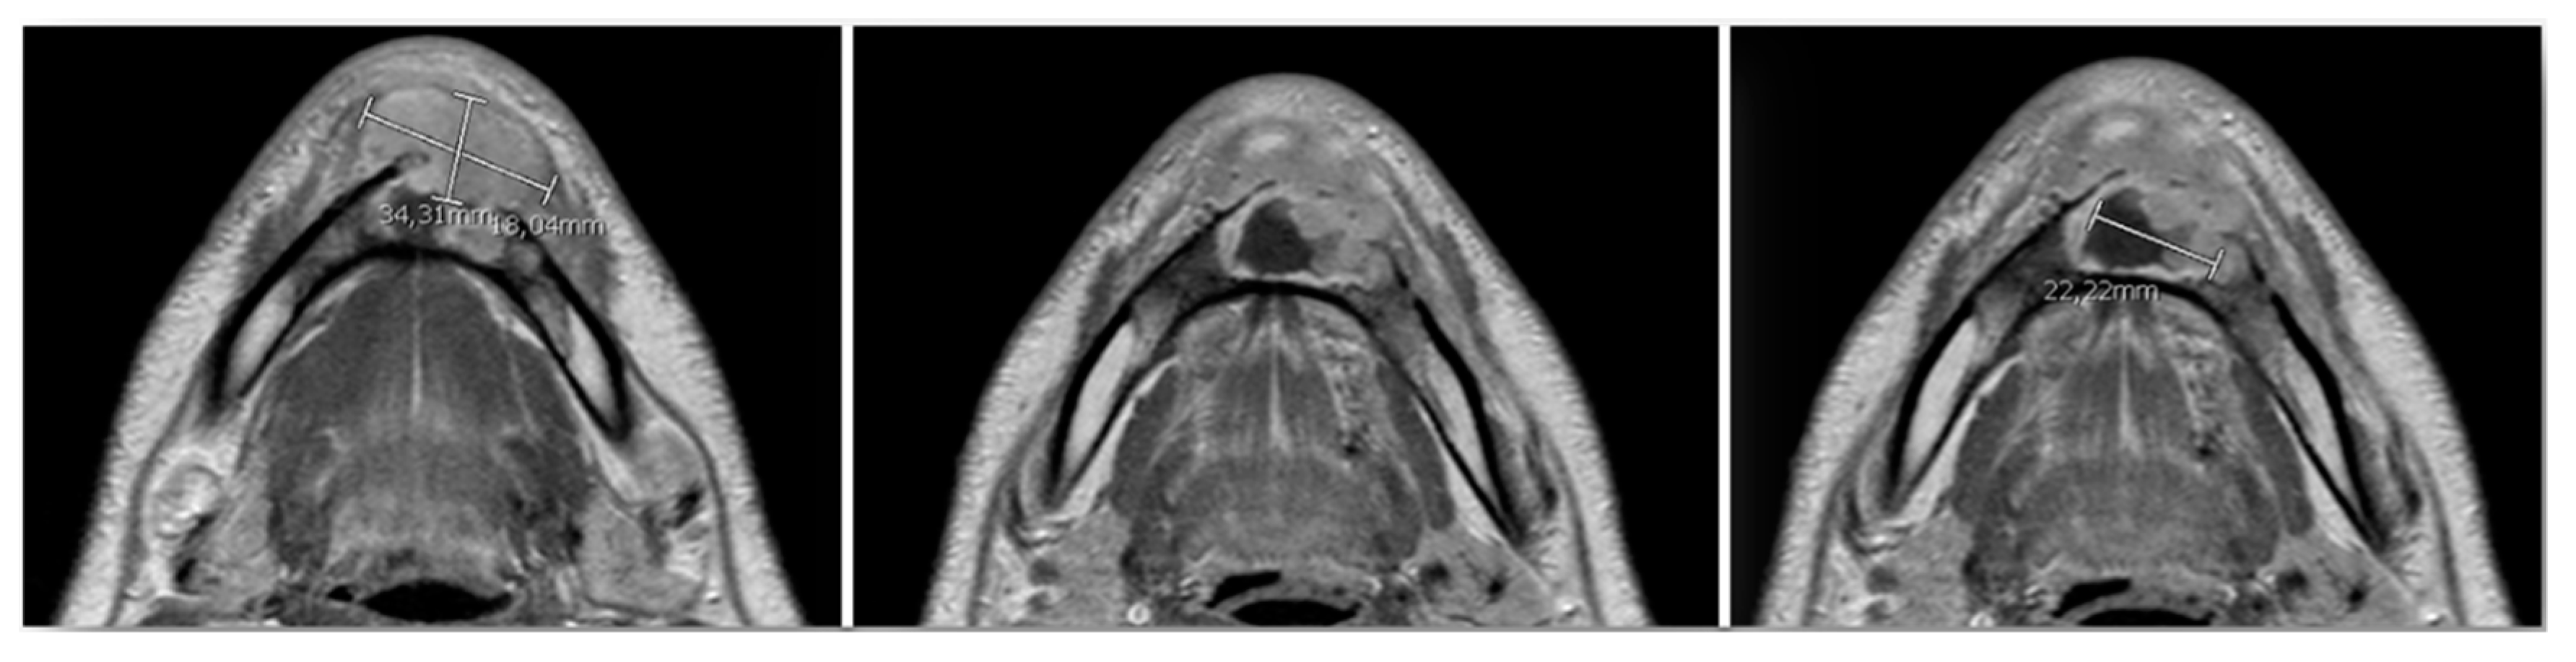

The clinical examination did not highlight any comorbidity. The physical examination showed a mild swelling of the left anterior mandible (Figure 3); there were no palpable lymphadenopathies. No mucosal ulceration in the inferior oral vestibule, neither oral fistula was detectable; no purulent discharge (Figure 4a) occurred after the last antibiotic therapy. The patient was a smoker (3.6 pack/year) and stopped his smoking habit 1 year before the hospitalization. He drank beer occasionally.

Figure 3.

Preoperative pictures. (a) Frontal view; (b) side view.

Figure 11.

Forty-five-days post-operative condition. (a) Frontal view; (b) side view; (c) intraoral picture; (d) Rx orthopantomography.